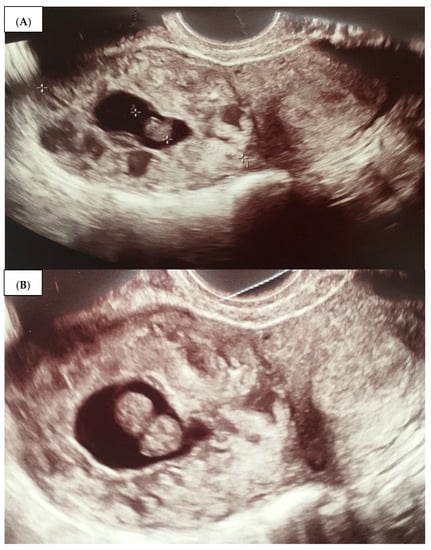

- An empty uterine cavity;

- A chorionic sac located eccentrically and at >1 cm from the lateral edge of the uterine cavity;

- A thin (<5 mm) myometrial layer surrounding the chorionic sac;

- The interstitial line sign;

- No double decidual sac sign, typically seen in the intrauterine pregnancy.

2.1. Case 1 (Patient A)

2.2. Case 2 (Patient B)